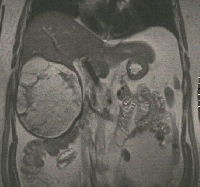

Δεξιά ηπατεκτομή (σωστική παρεγχύματος, parenchymal sparing) και δεξιά νεφρεκτομή για εχινοκοκκίαση

Πρόκειται για ασυμπτωματικό άνδρα ασθενή 54 ετών που υποβλήθηκε σε υπερηχογράφημα άνω κοιλίας στα πλαίσια προληπτικού ελέγχου, το οποίο ανέδειξε πολύχωρη εξεργασία του ήπατος. Ακολούθησε MDCT και MRI, κατά την οποία διαπιστώθηκε η ύπαρξη ηπατικής (CE3b) και νεφρικής (ΔΕ) εχινοκκοκίασης (εικόνες 1 & 2). Ο ασθενής έλαβε προεγχειρητική χημειοπροφύλαξη με albendazole για 4 εβδομάδες. Υποβλήθηκε σε δεξιά ηπατεκτομή (σωστική παρεγχύματος) και δεξιά νεφρεκτομή (εικόνες 3 & 4). Τα παρασκευάσματα φαίνονται στην εικόνα 5. Έλαβε εξιτήριο την 7η μετεγχειρητική ημέρα.